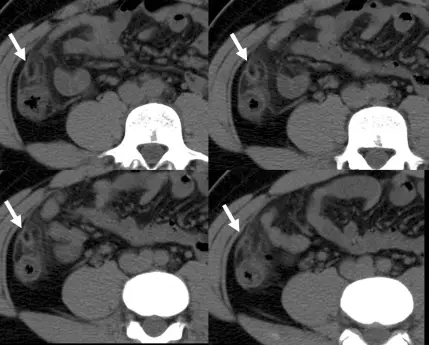

本題提供的電腦斷層影像為四個連續切面(2×2 格排列),均為**未注射顯影劑(non-contrast CT)**之腹部軸位影像。

各切面中可見右下腹(箭頭所指位置)有以下特徵性影像所見:

- 卵圓形脂肪密度病灶(fat-attenuation oval lesion):密度與腸系膜脂肪相近,呈低密度,大小約 1.5–3 cm,緊鄰升結腸(ascending colon)前側腸壁

- 高密度環繞邊緣(hyperattenuating ring sign):病灶周圍可見一圈薄層高密度環,代表發炎的臟層腹膜

- 周圍脂肪浸潤(fat stranding):病灶周圍可見模糊的脂肪密度增高,反映發炎反應向外擴散

- 結腸壁厚度正常:與憩室炎不同,此病灶鄰近的結腸壁無明顯增厚

- 未見闌尾腫大:無典型急性闌尾炎的「管狀腫大結構」

以上影像特徵高度符合**大網膜附屬物炎(epiploi